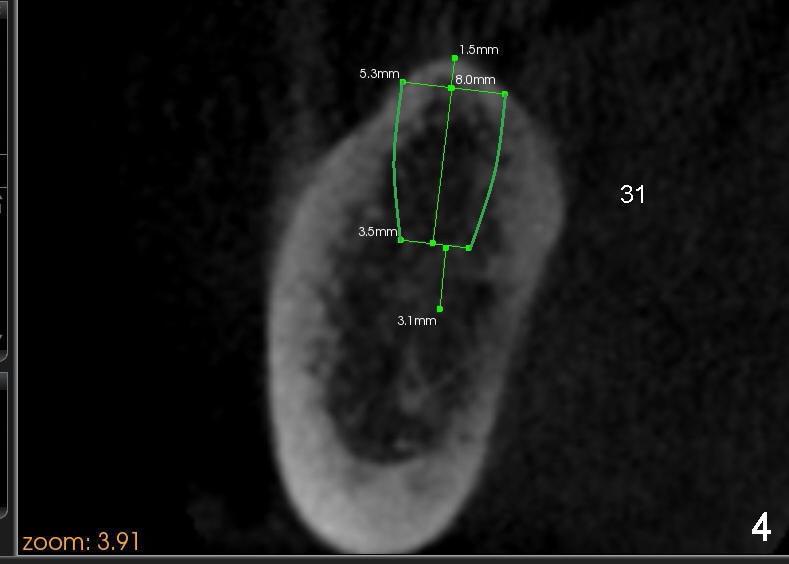

A 56-year-old lady requests implant placement at the sites of #18,30 and 31 (Fig.1, the last two first). CBCT shows preliminary design for implants at #30 and 31 (Fig.2 (sagittal section), 3,4 (coronal)).